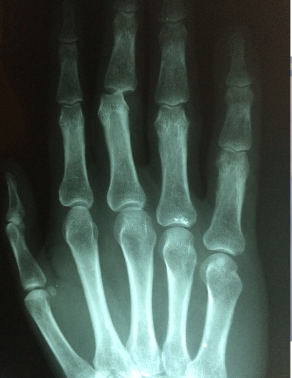

손가락 마디 통증 원인 1) 퇴행성 관절염

가장 대표적으로는 퇴행성 관절염이 있어요. 이는 손가락 마디 사이의 연골이 손상을 입거나 퇴행성 변화가 나타난 것을 말하는데요. 손가락 주위의 염증과 통증이 나타나고 손가락 끝마디가 예전보다 굵어지거나 돌출되는 특징도 있다고 해요. 보통 손을 자주 쓰는 직업군에서 더 잘 나타나게 되고, 손을 많이 사용하는 주부들에게서도 많이 발생하구요.

손가락 마디 통증 원인 2) 류마티스 관절염

손가락 부분에 염증이 생기게 되고 갈수록 범위가 커지구요. 손가락 두번째 마디에서 느껴지는 통증이 특징이에요. 이런 부분만 봐도 다르긴한데 추가로 어떤 차이점이 있는지 알려드릴게요

퇴행성관절염과 류마티스 관절염 차이

1) 퇴행성 관절염

- 많이 사용한 관절이 붓고 아프다

- 비대칭적인 통증

- 손가락 끝마디가 아프다

- 기상시 뻣뻣한 증상이 30분 이내로 가라앉는다

- 운동 후와 저녁에 아프고 휴식으로 통증이 완화된다

2) 류마티스 관절염

- 여러 관절이 동시에 붓고 열이 난다

- 좌우대칭적인 통증

- 손가락 가운데 마디가 아프다

- 기상시 뻣뻣한 증상이 1시간 이상 지속된다

- 식욕이 줄고 쉽게 피로해진다